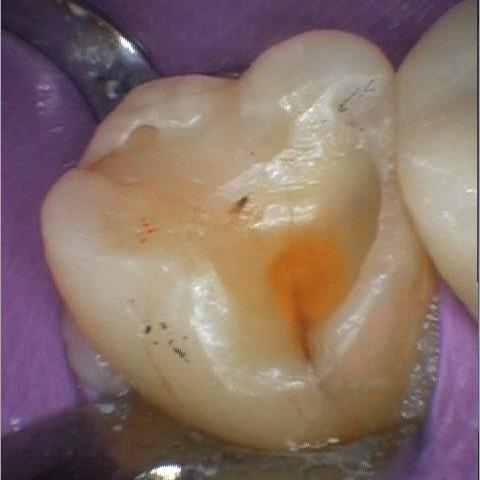

This patient suffered from a combination of acid erosion and grinding, which led to accelerated wear on her lower right molar. The enamel had been lost on the chewing surface and the underlying tooth structure was exposed. A conservative tooth-colored composite filling was placed to restore function and protect the tooth.

Before